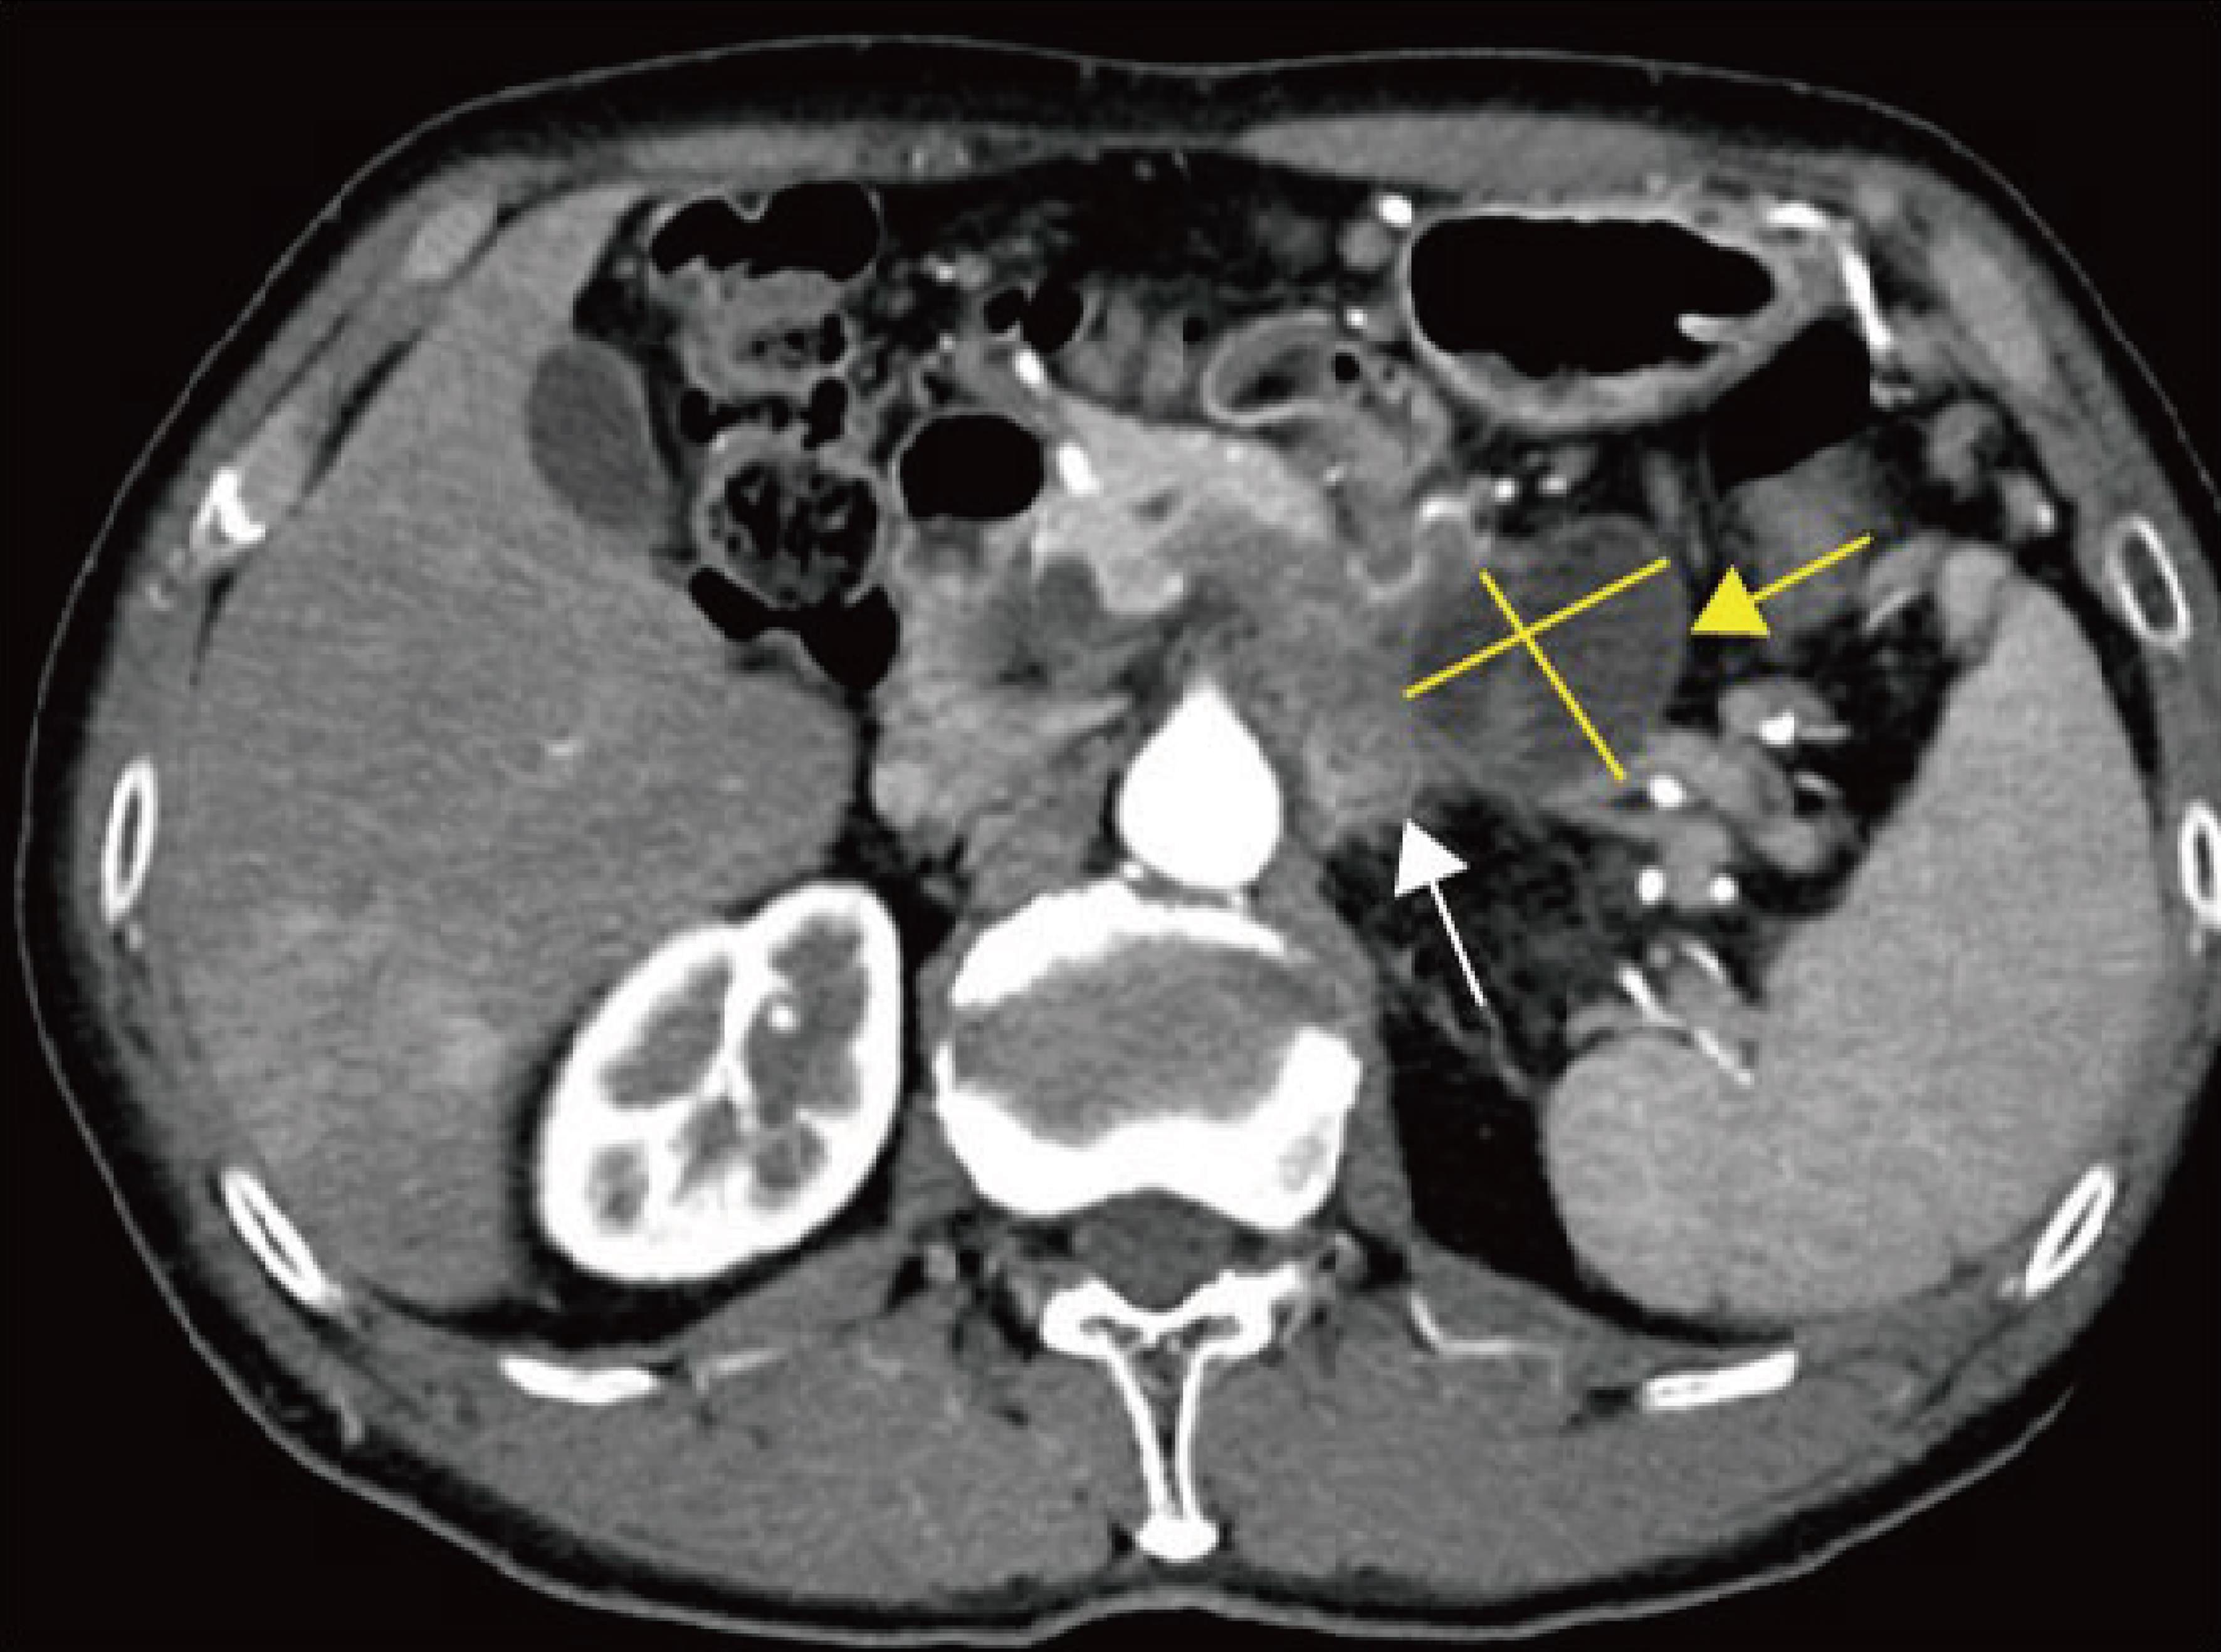

Explanation: Alcohol and gallstones are the most important etiologies of acute pancreatitis. Pancreatic cancer is a relatively uncommon cause, with an incidence of 0.9% to 3.6%.94 Mujica et al.95 hypothesized possible mechanisms by which pancreatic cancer induces acute pancreatitis, including mechanical obstruction of the pancreatic duct, ischemia caused by malignant tumor cells obstructing blood vessels, and direct activation of pancreatic enzymes by tumor tissue. The presence of obstructive pancreatitis is assessed based on suspicious masses, main pancreatic duct interruption with upstream ductal dilation, pancreatic enlargement upstream, blurring of peripancreatic fat planes, and stranding edema.96,97 Studies have found that 59% of pancreatic cancer cases were initially misdiagnosed as acute pancreatitis due to inflammatory changes masking underlying masses or secondary signs.98 Tummala et al.99 studied 218 patients with acute pancreatitis undergoing EUS-FNA and identified 38 cases of pancreatic cancer diagnosed promptly after the first episode of acute pancreatitis, with a resection rate of 39%, thereby improving patient survival. Therefore, in patients with acute pancreatitis after excluding common causes such as alcohol and gallstones, careful evaluation of pancreatic imaging is warranted to identify potential underlying malignancy,50,99,100 and this should be explicitly stated in imaging reports (Fig. 5).

Pancreatic cancer with surrounding obstructive inflammation.

Fig. 5  Pancreatic cancer with surrounding obstructive inflammation.

Axial arterial late-phase computed tomography (CT) image shows a hypodense mass in the pancreatic body and tail (white arrow), with patchy peripancreatic inflammatory infiltration (yellow arrow).